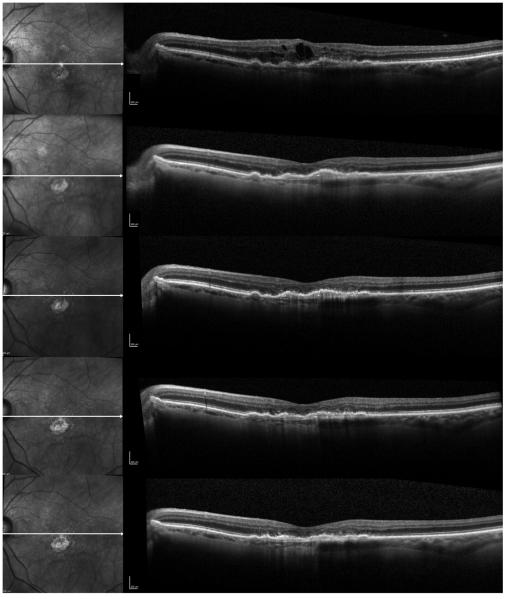

Figure 2.

A case of an 82-year-old female with recurrent fluid who has received 13 previous bevacizumab injections, and was subsequently switched to every 8 weeks intravitreal aflibercept injections. Progression scans going through the fovea at baseline and at subsequent follow-ups at 1 month, 2 months, 4 months, and 6 months after switching to aflibercept show progressive flattening of the subfoveal fibrovascular pigment epithelial detachment (PED) and resolution of the intraretinal fluid (IRF). Photoreceptor layer appears disrupted in the fovea.